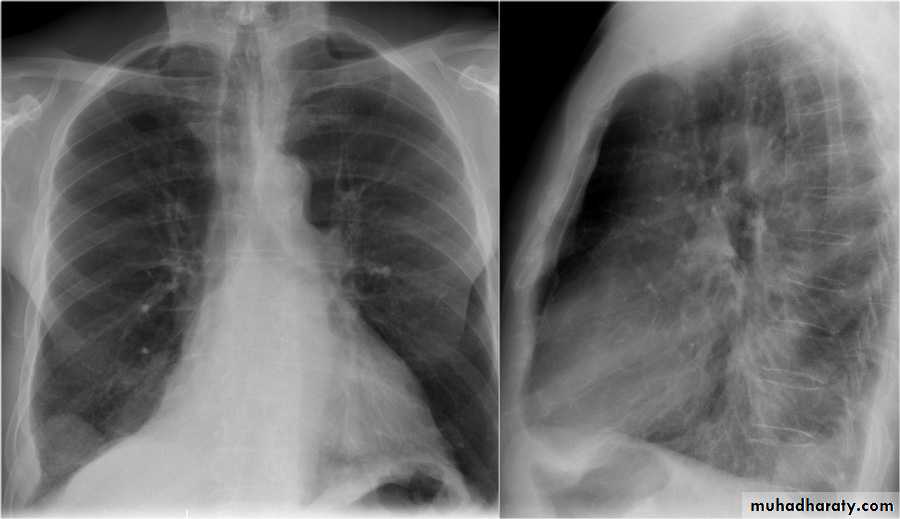

History: dyspnea, weight loss, dehydration with poor immunity

History; too shy to take of his shirt in the pool!